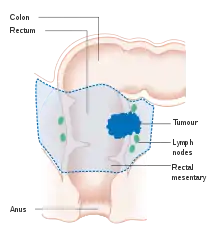

If the cancer is found at a very early stage, it may be removed during a colonoscopy using a variety of techniques including EMR and ESD.[6] For people with localized cancer, the preferred treatment is complete surgical removal with adequate margins, with the attempt of achieving a cure. The procedure of choice is a partial colectomy (or proctocolectomy for rectal lesions) where the affected part of the colon or rectum is removed along with parts of its mesocolon and blood supply to facilitate removal of draining lymph nodes. This can either be done by an open laparotomy or laparoscopically, depending on factors related to the individual person and lesion factors.[18] The colon may then be reconnected or a person may have a colostomy.[6]